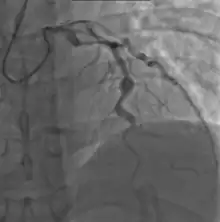

Heart complications are the most important aspect of Kawasaki disease, which is the leading cause of heart disease acquired in childhood in the United States and Japan.[29] In developed nations, it appears to have replaced acute rheumatic fever as the most common cause of acquired heart disease in children.[13] Coronary artery aneurysms occur as a sequela of the vasculitis in 20–25% of untreated children.[50] It is first detected at a mean of 10 days of illness and the peak frequency of coronary artery dilation or aneurysms occurs within four weeks of onset.[46] Aneurysms are classified into small (internal diameter of vessel wall <5 mm), medium (diameter ranging from 5–8 mm), and giant (diameter > 8 mm).[29] Saccular and fusiform aneurysms usually develop between 18 and 25 days after the onset of illness.[13]

Even when treated with high-dose IVIG regimens within the first 10 days of illness, 5% of children with Kawasaki disease develop at the least transient coronary artery dilation and 1% develop giant aneurysms.[51][52][53] Death can occur either due to myocardial infarction secondary to blood clot formation in a coronary artery aneurysm or to rupture of a large coronary artery aneurysm. Death is most common two to 12 weeks after the onset of illness.[13]

Many risk factors predicting coronary artery aneurysms have been identified,[19] including persistent fever after IVIG therapy,[54][55] low hemoglobin concentrations, low albumin concentrations, high white-blood-cell count, high band count, high CRP concentrations, male sex, and age less than one year.[56] Coronary artery lesions resulting from Kawasaki disease change dynamically with time.[3] Resolution one to two years after the onset of the disease has been observed in half of vessels with coronary aneurysms.[57][58] Narrowing of the coronary artery, which occurs as a result of the healing process of the vessel wall, often leads to significant obstruction of the blood vessel and the heart not receiving enough blood and oxygen.[57] This can eventually lead to heart muscle tissue death, i.e., myocardial infarction (MI).[57]

- Angiography was historically used to detect coronary artery aneurysms, and remains the gold standard for their detection, but is rarely used today unless coronary artery aneurysms have already been detected by echocardiography.